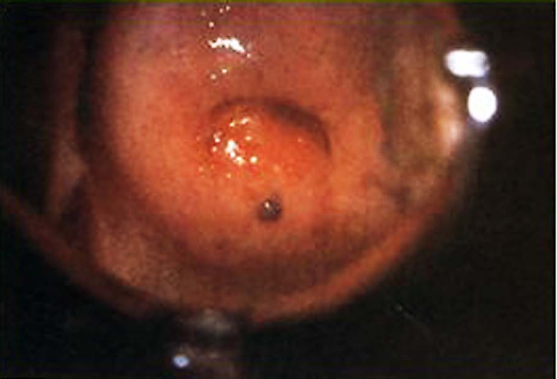

子宫颈内异症